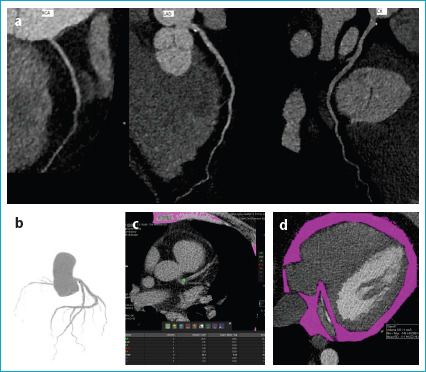

Methods: We retrospectively evaluated a total of consecutive 688 patients who were either asymptomatic but had a positive family history or had typical or atypical symptoms suggesting the presence of CAD. They all underwent CCTA examination with multiplanar reformat (MPR), maximal intensity projection (MIP), and myocardial three-dimensional (3D) volume rendering (VRT) images were obtained. We calculated CCS, coronary artery plaque stenosis degrees, the number of main coronary arteries involved and the EFVs for each patient. Finally, the relationship between the EFVs and all other parameters was analyzed by performing the Pearson and Spearman correlation analysis.